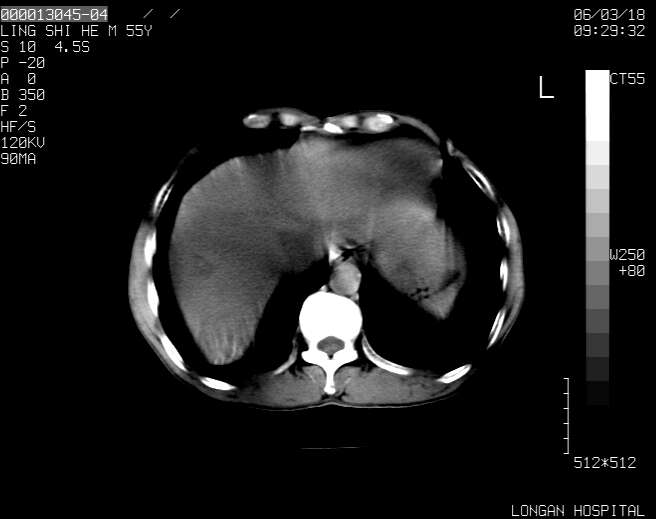

以下是引用guzhongliangddd在2006-3-21 22:13:00的发言:[br]病灶主要位于肝右叶的后份,内见异常血管,门脉主干及右支受侵{提示有癌栓形成},门腔间隙内见增大淋巴结。肝左叶内未见异常。

以下是引用zhuxinli在2006-3-22 1:23:00的发言:[br][br] 病灶主要位于肝右叶的后份,内见异常血管 .门脉右支截断,右叶前段早期强化(考虑动静脉漏),腹膜后肿大淋巴结,病灶逐渐强化,考虑为胆管细胞癌[br]